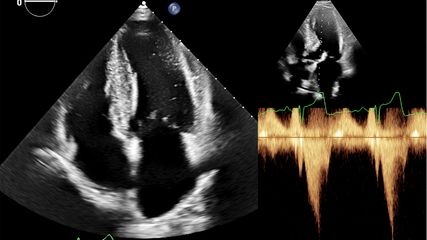

Kinder, die mit kongenitalen Herzvitien geboren werden, erreichen mittlerweile zu mehr 90% das Erwachsenenalter. Mit dem Update ihrer Leitlinie zum Management kongenitaler Vitien bei erwachsenen Patienten liefert die ESC detaillierte Empfehlungen für den Umgang mit den Spätkomplikationen dieser Erkrankungen.

Die Guideline gibt detaillierte Empfehlungen zum Management von Komplikationen kongenitaler Vitien, wie zum Beispiel der pulmonalen Hypertonie, die sich häufig bei Patienten mit Shuntläsionen einstellt. Die Leitlinie betont dabei die Notwendigkeit einer invasiven Abklärung, wenn Patienten mit einer Shuntläsion Hinweise auf erhöhten pulmonalarteriellen Druck zeigen. Das weitere Vorgehen richtet sich nach dem pulmonalen Gefässwiderstand. Ist dieser niedrig, können alle Shunts geschlossen werden. Für höheren Widerstand (mehr als drei Wood‘s Units) gibt die Guideline detaillierte Empfehlungen, welche Shunts unter welchen Umständen verschlossen werden können. Für Patienten, die eine medikamentöse Behandlung ihres Lungenhochdrucks benötigen, werden Empfehlungen in Anlehnung an die PAH-Leitlinie der ESC gegeben – die Therapie soll sich also nach der Risikobewertung richten. Für den Shuntverschluss gibt die Guideline einen Algorithmus vor. Detailliert abgehandelt werden Anomalien des linksventrikulären Ausflusstrakts und der Aortenklappe. Die Frage, ob eine Intervention erforderlich ist, wird anhand der Lokalisation der Läsion, der Symptome (auch unter Provokation) sowie möglicher resultierender Schäden an Ventrikel oder Klappe beantwortet. Neu ist eine Empfehlung für die chirurgische Reparatur der Aortenklappe bei bestimmten Patienten mit Marfan-Syndrom.

Im Falle einer Stenose der Pulmonalklappe ist die Ballonvalvuloplastie die Intervention der Wahl, sofern es sich nicht um eine dysplastische Klappe handelt. Indikation für den Klappenersatz besteht bei symptomatischen Patienten mit schwerer Stenose, wenn eine interventionelle Behandlung nicht möglich ist. Darüber hinaus werden Faktoren gelistet, die auch in Abwesenheit von Symptomen eine Indikation für den Klappenersatz bedeuten können. Regurgitation durch die Pulmonalklappe ist eine häufige Spätkomplikation bei Patienten nach chirurgisch behandelter Fallot-Tetralogie. Bei symptomatischen Patienten mit ausgeprägter Regurgitation bzw. bestimmten Risikofaktoren besteht eine Indikation zum Klappenersatz. Wenn anatomisch machbar, ist dabei – laut der neuen Empfehlung – der Katheterintervention der Vorzug zu geben